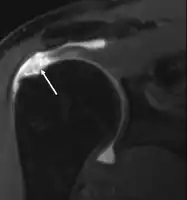

MRI

MRI of normal shoulder intratendinous signal

MRI of rotator cuff full-thickness tear

Magnetic resonance imaging (MRI) and ultrasound[46] are comparable in efficacy and helpful in diagnosis, although both have a false positive rate of 15–20%.[47] MRI can reliably detect most full-thickness tears, although very small pinpoint tears may be missed. In such situations, an MRI combined with an injection of contrast material, an MR-arthrogram, may help to confirm the diagnosis. It should be realized that a normal MRI cannot fully rule out a small tear (a false negative) while partial-thickness tears are not as reliably detected.[48] While MRI is sensitive in identifying tendon degeneration (tendinopathy), it may not reliably distinguish between a degenerative tendon and a partially torn tendon. Again, magnetic resonance arthrography can improve the differentiation.[48] An overall sensitivity of 91% (9% false negative rate) has been reported, indicating that magnetic resonance arthrography is reliable in the detection of partial-thickness rotator cuff tears.[48] However, its routine use is not advised, since it involves entering the joint with a needle, with the potential risk of infection. Consequently, the test is reserved for cases in which the diagnosis remains unclear.